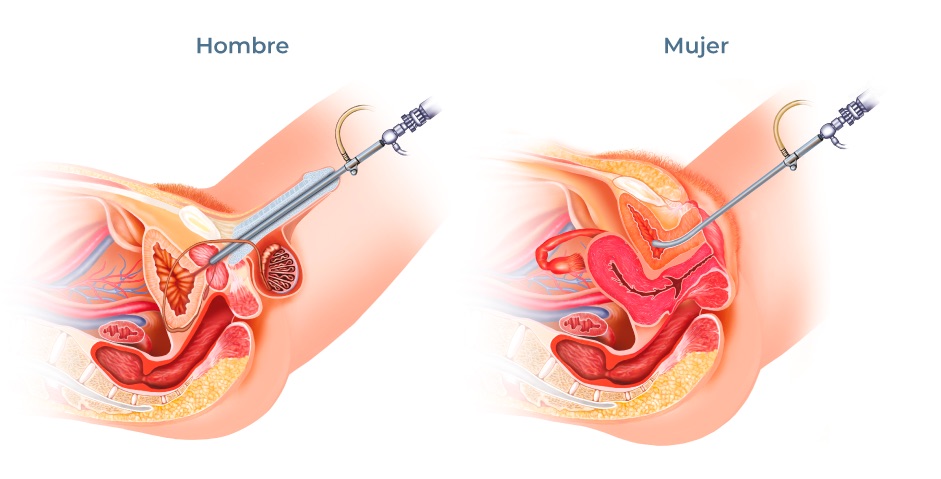

La uretromeatotomía es un procedimiento quirúrgico ambulatorio que se realiza para ampliar el meato uretral y el segmento distal de la uretra cuando existe una estrechez que dificulta la salida normal de la orina 🚻

🏥 ¿Cómo se realiza?

- 1902056: Dilatación uretral instrumental.

- 1902057: Uretrotomía interna endoscópica.

- 1902074: Uretroplastia.